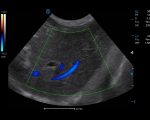

PW mode provides accurate hemodynamic and spectral information to detect subtle changes in blood flow and enable quantitative measurement.

CW mode sensitively detects and visualizes high-velocity blood flow signals, which is helpful for the diagnosis of early vascular disorders in animals.